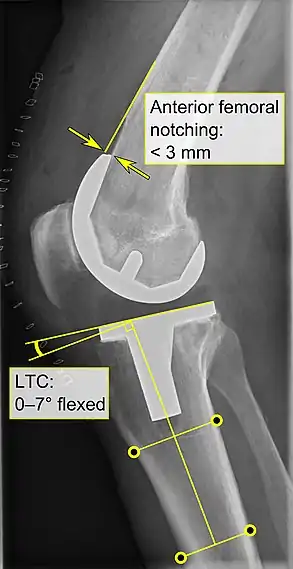

Knee replacement is routinely evaluated by X-ray, including the following measures: